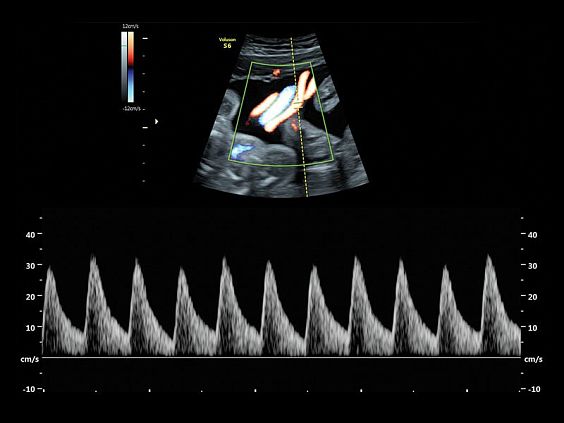

Клинические изображения

- Работа в В-, М-режимах, наличие импульсно-волнового, цветного допплеровского картирования, тканевого, энергетического и высокочувствительного направленного энергетического допплера (HD-Flow), тканевая гармоника

- Работа в В-, М-режимах, наличие импульсно-волнового, цветного допплеровского картирования, тканевого, энергетического и высокочувствительного направленного энергетического допплера (HD-Flow), тканевая гармоника

- B-Flow - режим недопплеровской визуализации кровотока.

- CWD - опция постоянно-волнового допплера

- Усовершенствованное цветовое доплеровское картирование — для более детального исследования анатомии и функционального состояния сосудистой системы.